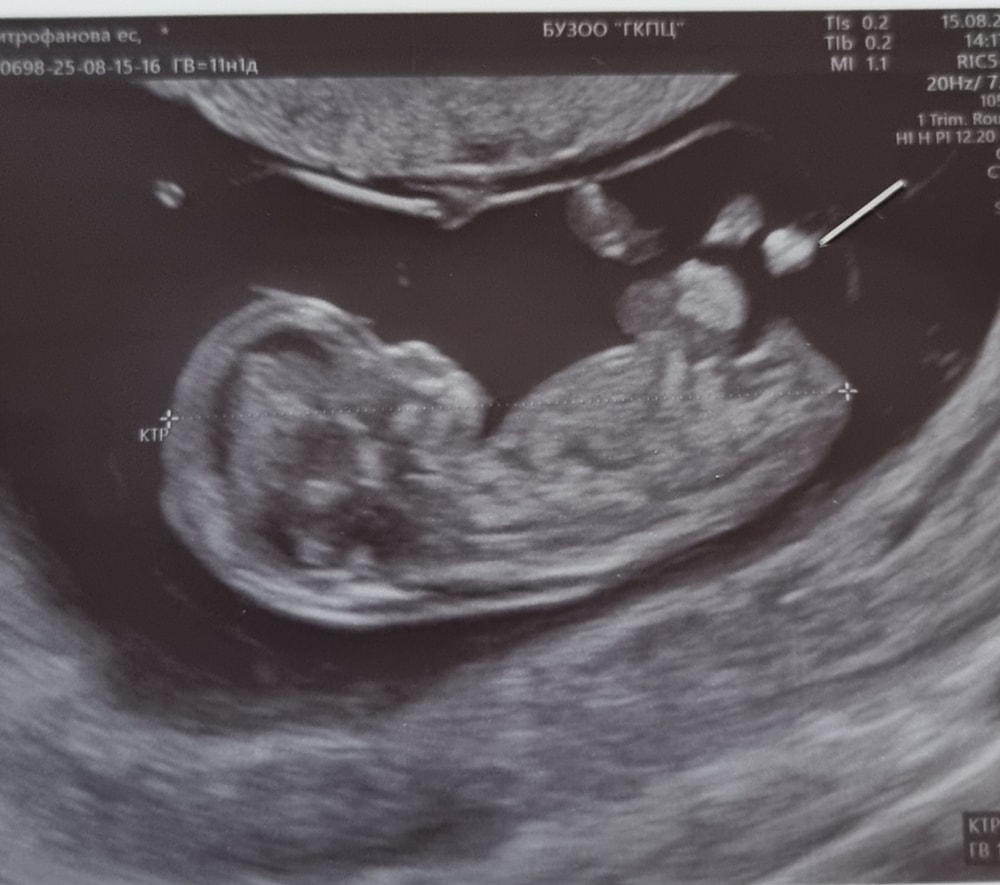

Здравствуйте девочки! Сходила на УЗИ. Сб есть.. КТР 3.4. 6 недель только сегодня исполнилось. В тот раз не правильно поставили срок 6 нед 2 дня. СБ есть но не прям яркое. Сказали маленький срок. Поэтому плохр слышно. ПЯ вырос до 21. Спасибо вам большое! 💜🌸